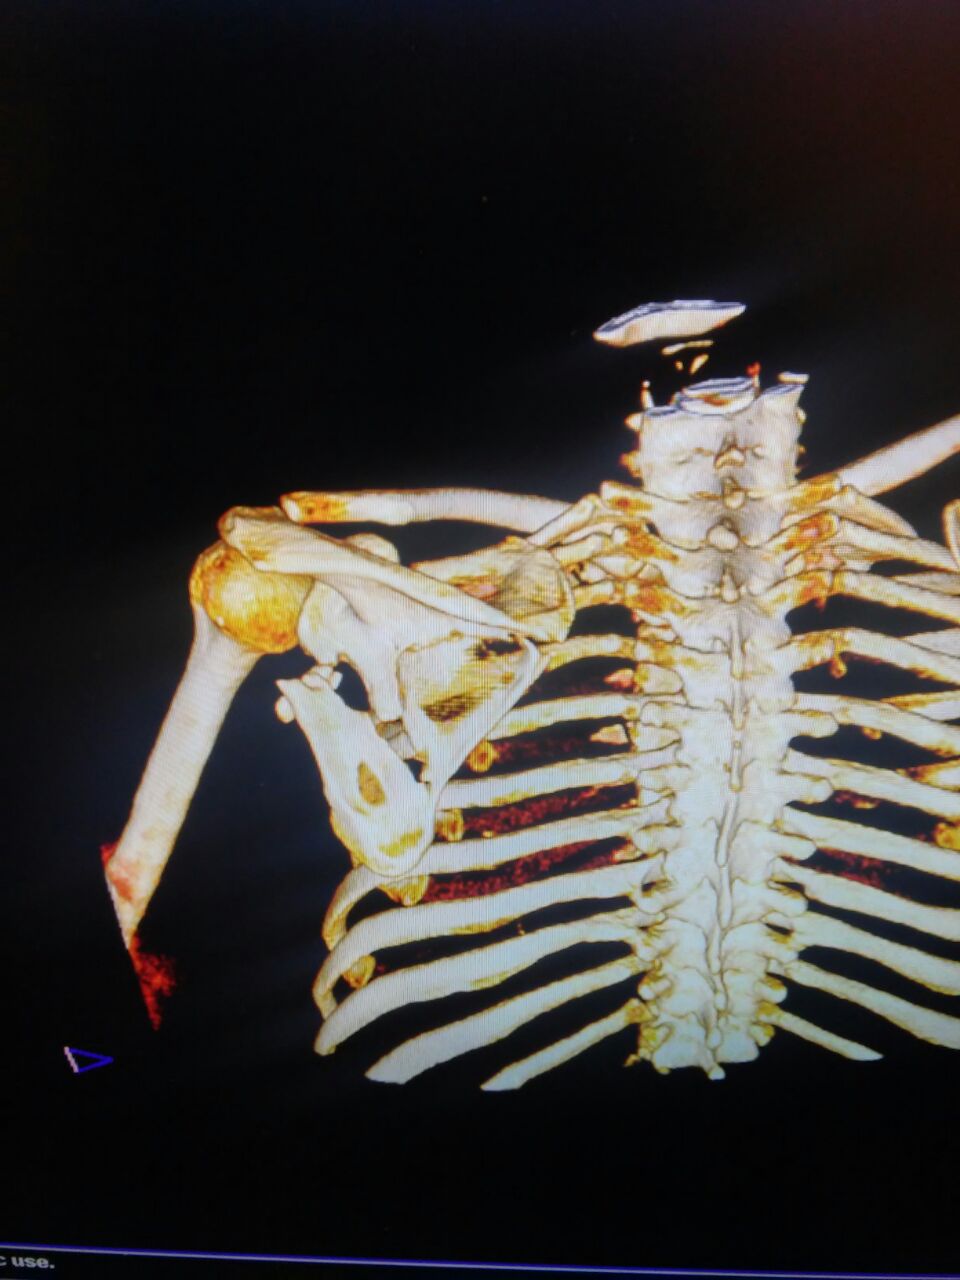

Данный перелом относится к перелому тело лопатки и несмотря на наслоение, где лопатка покрывает грудную клетку, но можно увидеть три большие фрагмента, которые находятся в разных плоскостях. Суставная поверхность расположена намного медиальнее, что нарушает бланс мышц, которая в последующем может привести к ограничению движения верхного пояса. Расположение суставной поверхности нуждается в уточнении дополнительными исследованиями, включая КТ и стандартные снимки плеча.!